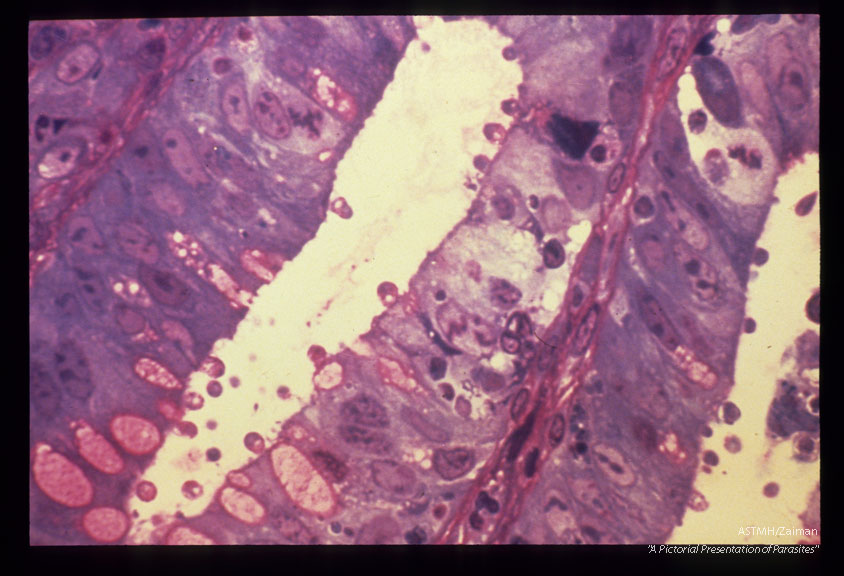

Rectal biopsy, epoxy thick section.

Cryptosporidium

Description: Rectal biopsy, epoxy thick section.